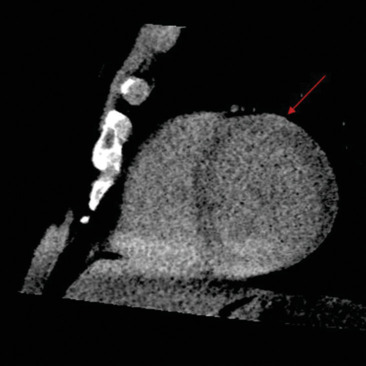

In the evaluation of cardiomyopathies, cardiac computed tomography (CCT) is predominantly used for assessing congenital or acquired coronary artery diseases as a potential etiology underlying the observed myocardial abnormalities. However, its utility is expected to expand. We present a case of an asymptomatic patient with claustrophobia who sought medical attention due to frequent ventricular beats. The resting electrocardiogram revealed repolarization abnormalities characterized by flattened T-waves in the lateral leads and low QRS voltages in the peripheral leads, whereas transthoracic echocardiography was normal. CCT accurately identified hypodense areas indicative of fibrofatty infiltration within the inferolateral and anterior walls of the left ventricle. Furthermore, late iodine contrast-phase imaging revealed subepicardial late enhancement striae in the same regions. These imaging findings were pivotal in establishing a diagnosis of left-dominant arrhythmogenic cardiomyopathy. This clinical vignette underscores the potential of CCT in tissue characterization, particularly when cardiac magnetic resonance imaging is contraindicated or unavailable.

Abstract Image